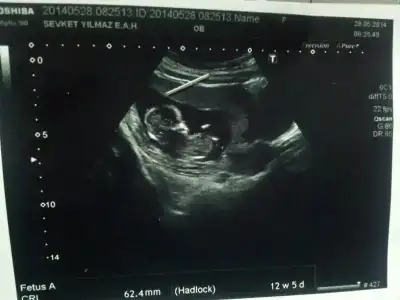

Kızlar benim bebeğimin de cinsiyetini tahmin eder misiniz ? İkili test sırasında Oğlan'a benzettim ama bana güvenme dedi ultrasonu çeken doktor. Kendi doktorum değildi. Devlette yaptırmıştım ikili testi. Çok merak ediyorum.

İlk resimde 10+2 ydik.

ikinci resimde sat 13+2 ultrason 12+5 ti. Gerçi hep sat ile ultrason uyumlu gittim. Devletteki ultrason bozdu olayı :) $IMG.webp $1401271843618.webp

Yorumlarınızı bekliyorum.